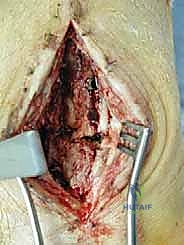

الخطوة الثالثة: إزالة المفصل القديم (Explant Removal)

يتم استخراج المكونات المعدنية والبلاستيكية لمفصل (Agility) القديم بحرص بالغ للحفاظ على ما تبقى من العظم السليم.

الخطوة الرابعة: تنظيف العظم والترقيع (Debridement and Bone Grafting)

يتم تنظيف الأنسجة الملتهبة والأكياس العظمية. ونظراً لأن مفصل (Agility) يترك فراغاً كبيراً بعد إزالته، يتم استخدام طعوم عظمية (Autograft من حوض المريض أو Allograft من بنك العظام) لملء الفراغات وبناء أساس قوي.